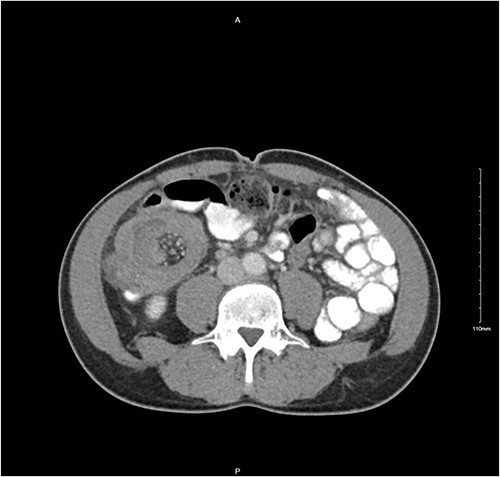

A 56-year-old male was diagnosed with a 4-day history of worsening, cramping left-sided lower abdominal pain and persistent vomiting. The patient had experienced intermittent bouts of similar pain in the previous few months; however, the sustained nature of the pain on this occasion prompted his presentation. Clinical examination elicited lower abdominal tenderness, most marked in the right para-umbilical region. He was an otherwise healthy patient, with no pertinent medical history. Initial investigations revealed a white cell count of 11.78 × 109/L with an associated mild neutrophilia of 9.29 × 109/L. His C-reactive protein was significantly elevated at 130 mg/L, with remaining haematological tests otherwise unremarkable. A computed tomography (CT) scan with intravenous contrast of the abdomen and pelvis was performed which identified a long segment (21 cm) of intussusception involving the distal small bowel, caecum and ascending colon and entirety of transverse colon, including mesentery (Fig. 1). A 5.5-cm hypodense mass was noted within the splenic flexure of the transverse colon which acted as a lead point for intussusception (Fig. 2). There was no pathological small bowel dilatation. Radiologically, the suggested differential diagnosis included gastrointestinal stromal tumour, carcinoid tumour, leiomyosarcoma, lymphoma or benign pathologies such as leiomyoma. The patient proceeded to theatre whereby a formal resection by means of extended right hemicolectomy and primary anastomosis was performed. Histological analysis demonstrated an ileal myxoma to be the causative pathology. The patient had an unremarkable post-operative course and was discharged well 1 week post-operatively.

Transverse CT image demonstrating long segment of small bowel telescoping towards splenic flexure of the colon.